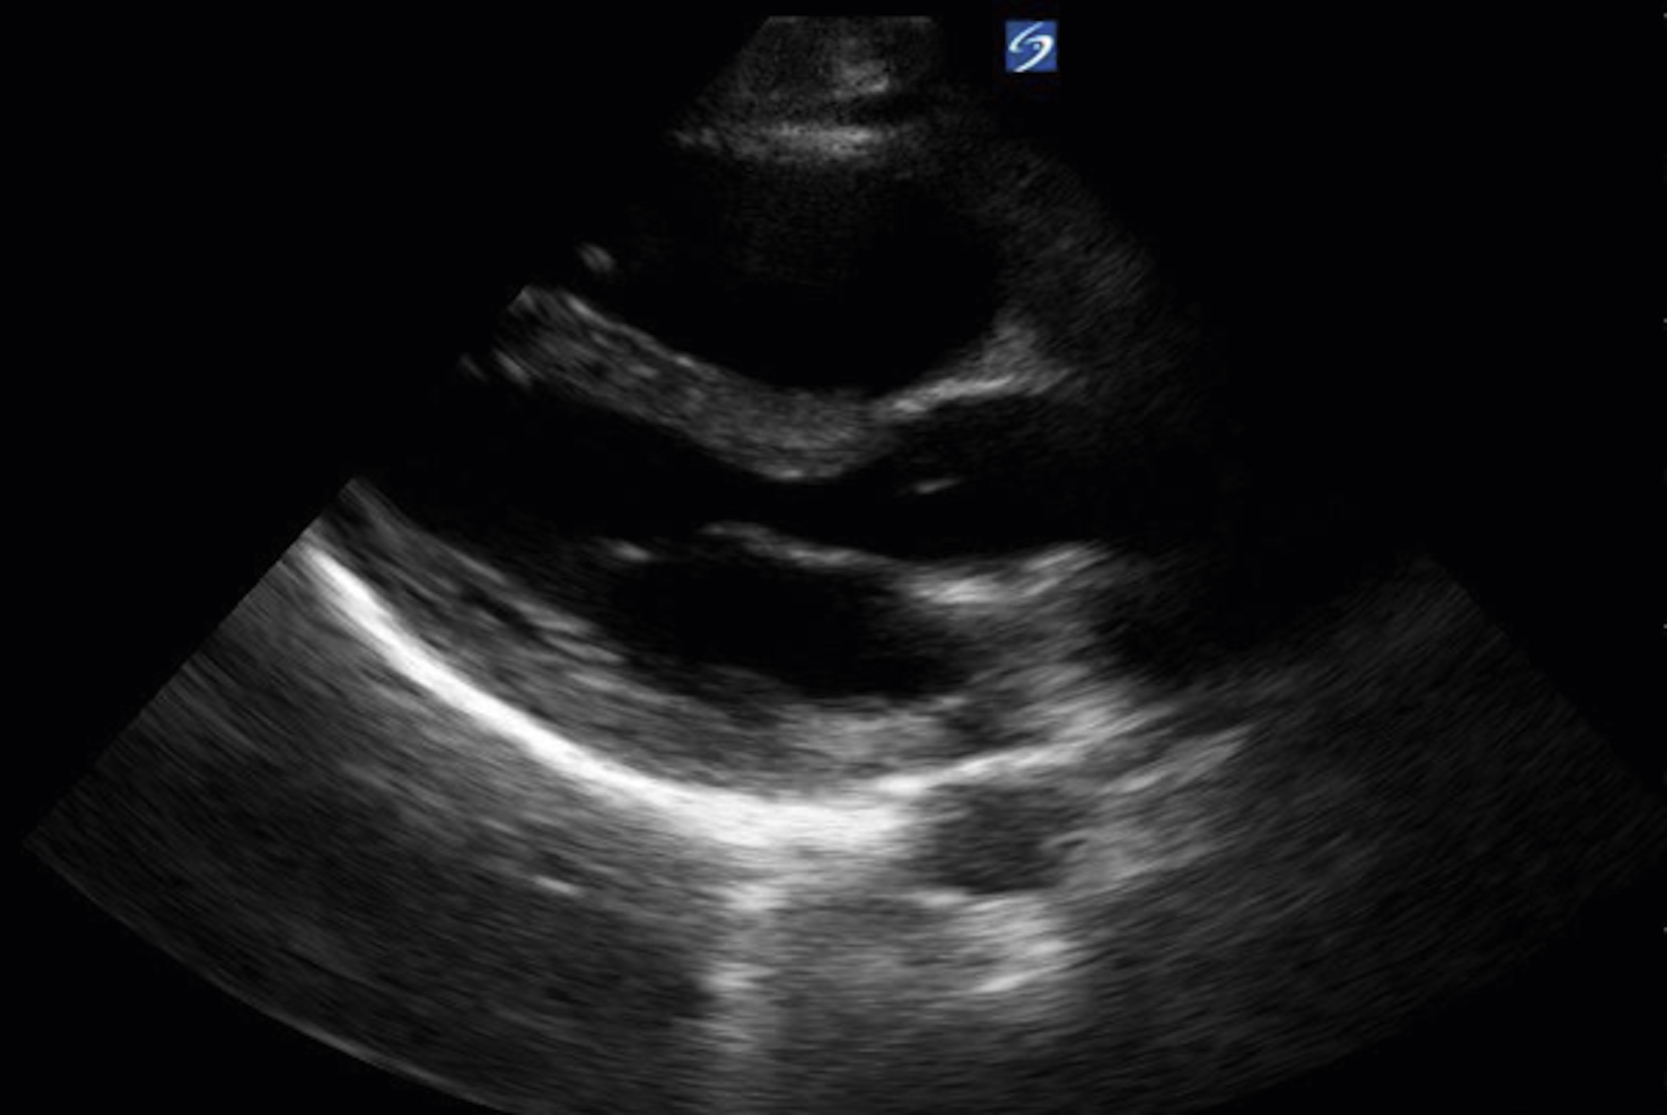

Pericardial fluid is typically anechoic, although it can contain internal echoes in cases of pericardial hemorrhage or infection. Large pericardial effusions are usually circumferential but can be loculated. As a result, assessment for pericardial effusion should include multiple views, when feasible, to confirm diagnosis and to avoid mistaking the epicardial fat pad for a pericardial effusion. Although cardiac tamponade is a clinical diagnosis, there are several suggestive echocardiographic features, including diastolic collapse of the RV ( Video e3.9 ), loss of respiratory variation of the IVC ( Fig. e3.11 ), and transvalvular flow velocity paradoxus.

Fig. e3.11

Plethoric IVC showing where to take a measurement.